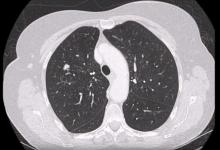

The authors present a video demonstrating redo lung resection by VATS to show that previous surgery on the thorax does not contraindicate a minimally invasive re-intervention. The literature on this topic currently consists of case reports and small case series. Although there is little in the literature on this subject, D’Amico and colleagues do not list redo surgery within the contraindications for VATS. The authors’ experiences confirm this. This video shows four lung resection procedures, highlighting specific techniques for the treatment of the different pathologies.

The authors conclude that not only is a previous cardiothoracic procedure not a contraindication for lung resection by VATS, but the magnification and angle of the optic can better show adhesions, especially at the apex and in the costophrenic recess, resulting in a safer dissection technique. Additionally, a thoracotomy could be harmful in these cases where the lung is tightly adherent to the parietal pleura.